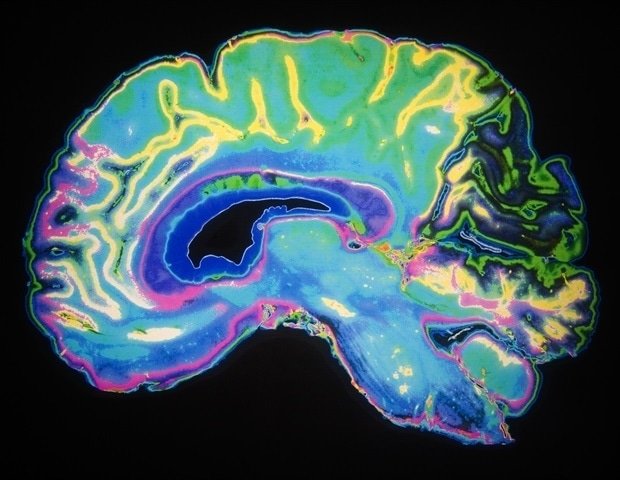

Neuroimaging investigations have also revealed extensive changes in brain network structure in various psychiatric conditions. When trained on the MRI data, the machine learning models demonstrated high accuracy in distinguishing schizophrenia patients from healthy individuals and identified distinct connectivity patterns associated with suicidal ideation in bipolar disorder and the impact of childhood trauma on depression.